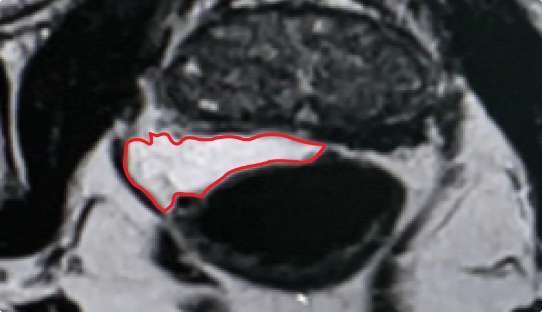

How hydrogel rectal spacer material impacts symmetrical implant placement

Symmetrical rectal spacer placement is important in order to offer complete coverage of the rectum during prostate radiation. Barrigel hydrogel spacer is the only sculptable spacer available. Due to its customization properties, it has been shown to achieve symmetrical placement >95% of the time.1 As a result of the quick polymerization of PEG Hydrogels, symmetrical placement is less achievable. In the PEG Hydrogel FDA clinical trial, symmetrical placement was achieved 49% of the time.2

PEG HYDROGEL

Implant Symmetry RESULTS2

49%